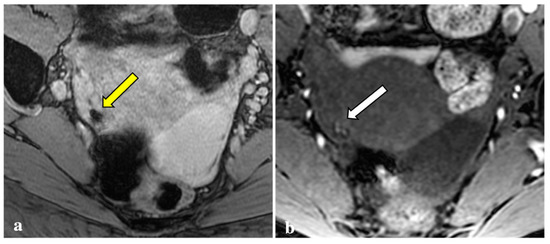

3.2. MRI Findings